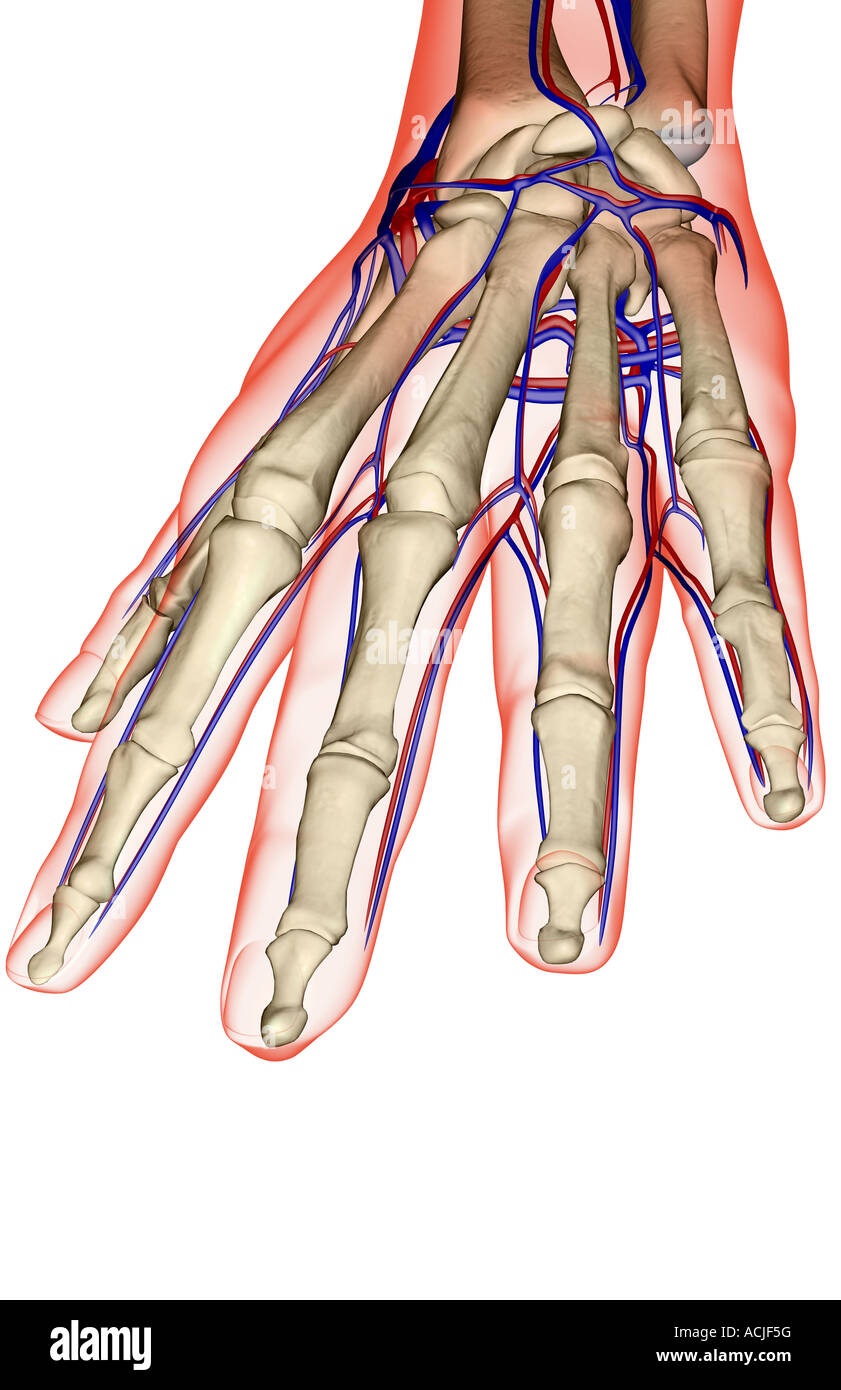

The blood supply of the hand Stock Photohttps://www.alamy.com/image-license-details/?v=1https://www.alamy.com/stock-photo-the-blood-supply-of-the-hand-13170027.html

The blood supply of the hand Stock Photohttps://www.alamy.com/image-license-details/?v=1https://www.alamy.com/stock-photo-the-blood-supply-of-the-hand-13170027.htmlRFACJF5G–The blood supply of the hand